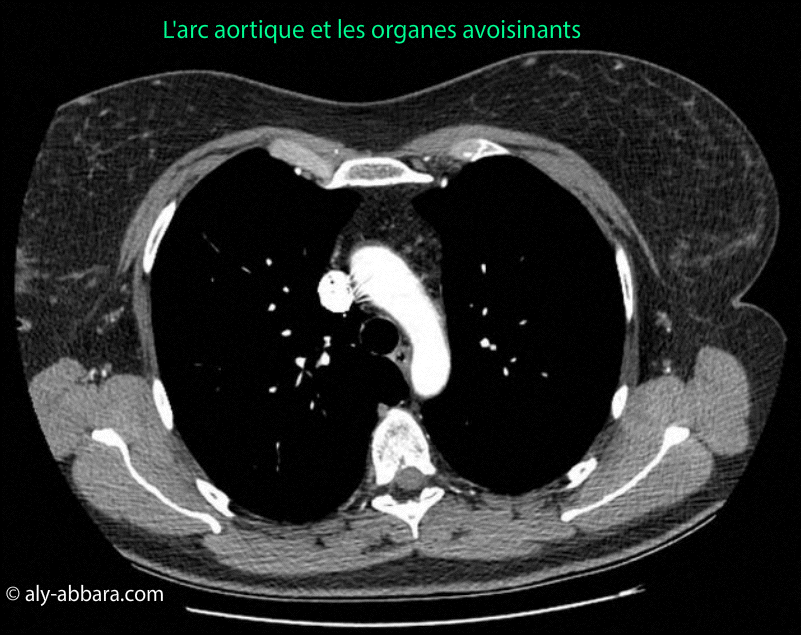

Images-scanner montrant l'arc aortique et ses rapports anatomiques avec les organes avoisinants

Images-scanner montrant l'arc aortique et ses rapports

anatomiques avec les organes avoisinants.